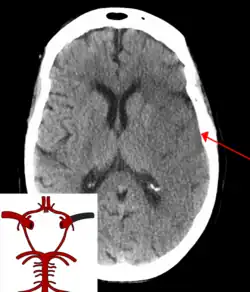

CT scan of the brain showing a massive, prior right-sided ischemic stroke from blockage of an artery. Changes on a CT may not be visible early on.[1]

CT scan of an intraparenchymal bleed (bottom arrow) with surrounding edema (top arrow)